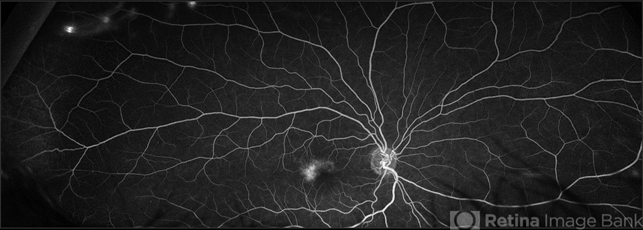

- macular telangiectasia type 2

Scanning laser ophthalmoscope

Optos California - Description

- 45-year-old African American, female with type 2 diabetes mellitus, showing bilateral, temporal macular telangectasis & peripheral microaneurysms